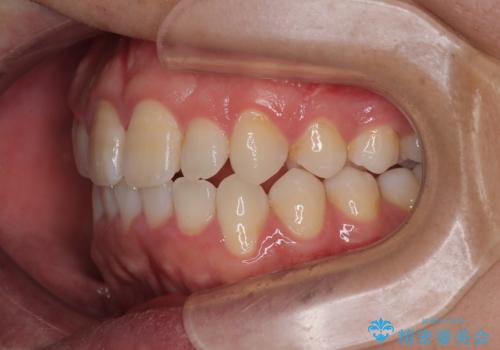

- 「上下の前歯がガタガタしているのが気になる」とのことで来院された患者様です。

上下顎前歯部に叢生(歯の重なり・ガタつき)を認め、見た目だけでなく、歯磨きのしにくさも気にされて来院されました。

- 矯正治療後の保定が不十分だと後戻り(元の位置に戻ろうとする動き)をします